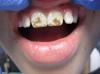

Екатерина Геранина Опубликовано 26 июня, 2013 Поделиться Опубликовано 26 июня, 2013 (изменено) У нас эндемическая зона по флюорозу. Показатели фтора в питьевой воде превышают норму в 10-15 раз,поэтому преобладают деструктивные формы флюорозаПару недель назад мальчик,8 летПараллельно проводится рем терапия с использовнием инд.капп Фото "до" и "после" Изменено 26 июня, 2013 пользователем Екатерина Геранина Ссылка на комментарий

Екатерина Геранина Опубликовано 28 июня, 2013 Поделиться Опубликовано 28 июня, 2013 Таким образом, Вы хотите сказать, что от применения описанной Вами методики исчезли коричневые пятна..?Нет,нет. В случае, показанном мною выше, деструктивная форма с глубокой пигментацией. Этим пятнам даже отбеливание не поможет и деструкцию нужно ж устранять. Меня,как я поняла,спрашивали просто про методику рем.терапии...В таких случаях, как я показала,-только реставрация,но препарирование избирательное было-только в измененных участках. В реставрации преобладали опаковые оттенки самые светлые,плюс чуть эмали. То есть подстраивалась под естеств. Рисунок зубаПозже после курса рем.терапии этому ребенку сделала латеральные резцы,не затрагивая проксимальные пов-ти беспрепаровочным методомА рем терапия-это с целью предотвращения появления новых пятен,то есть меловидные пятна и остаются меловидными,не переходя в подобную деструктивную форму.Если есть коричневые пятна...нужны более радикальные методы лечения. Ссылка на комментарий